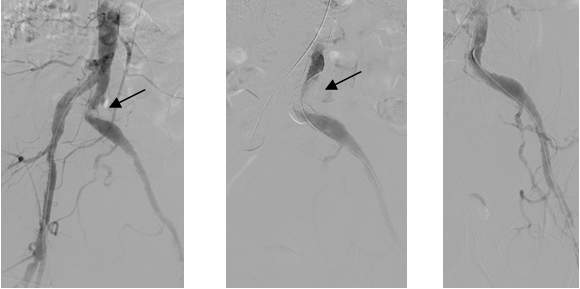

Figure 4. Primary stenting of an 80-90% stenosis on the distal portion of the left common iliac artery distal stenosis. Left and middle panel: stenosis is indicated by the arrow. Contrast medium was given from the aorta proximal to the stenosis (left panel) or the left common iliac artery distal from the stenosis.

Due to technical reasons (antegrade or retrograde puncture, contralateral or ipsilateral puncture, femoral or brachial puncture), prognosis and risks, three types of levels are distinguished: iliac (Figure 4), femoro-popliteal (Figure 5) and crural (infragenual) (Figure 6) endovascular therapy. The latter two composes the infrainguinal group. PTA and stent placement are usually technically easier (with the exception of long occlusions), have a longer patency and carry lower risk in the iliac group compared to the other two groups. Patency following crural PTA is the worse and carries the highest risk, therefore, it is usually indicated only in Fontaine stages III and IV. The number of amputation per capita in Hungary is larger than that in most other European countries. In patients with gangrene and diabetes mellitus, crural PTA may save a large number of amputations. In case of successful PTA, limb salvage rate is considerably higher than crural patency rate, since perfusion needed for a healing ulcer or gangrene is considerably higher than for the basic functions (collateral arteries may be sufficient for such purpose). Subintimal PTA is performed more and more frequently: when luminal recanalisation is technically not possible, intentional dissection is done using the hydrophilic guidewire along the occluded segment; then, distally to the occlusion, the guidewire is directed back to the normal lumen and a new channel is formed along the normal lumen–dissected channel–normal lumen route (Figure 5).

Figure 5. Subintimal percutaneous transluminal angioplasty (PTA). Panel A: Superficial femoral artery has been occluded from its origin with a stump (upper arrow). Refilling occurs at the distal SFA (lower arrow), total length of the occlusion is approximately 18 cm. Panel B: The white background („roadmap”) shows the profunda femoral artery. The guidewire (in black on the white background; arrow) is at the beginning of the occluded segment. Panel C: the guidewire forms a loop (arrow), and gradually proceeds into the subintimal space. Panel D: the tip of the guidewire reached the normal popliteal artery lumen, there is no loop formation any longer. Panel E: Following balloon dilation of the whole segment, SFA shows quick flow in its entire length.

Figure 6. Crural PTA. Left panel: the only crural vessel filling is the peroneal artery; the posterior tibial artery is filled only in the proximal segment; the plantar arch in its continuation is also filled. Middle panel: successful recanalisation of the posterior tibial artery was performed using the guidewire (dashed arrow). Right panel: following balloon dilation, posterior tibial artery is well filled (arrows).